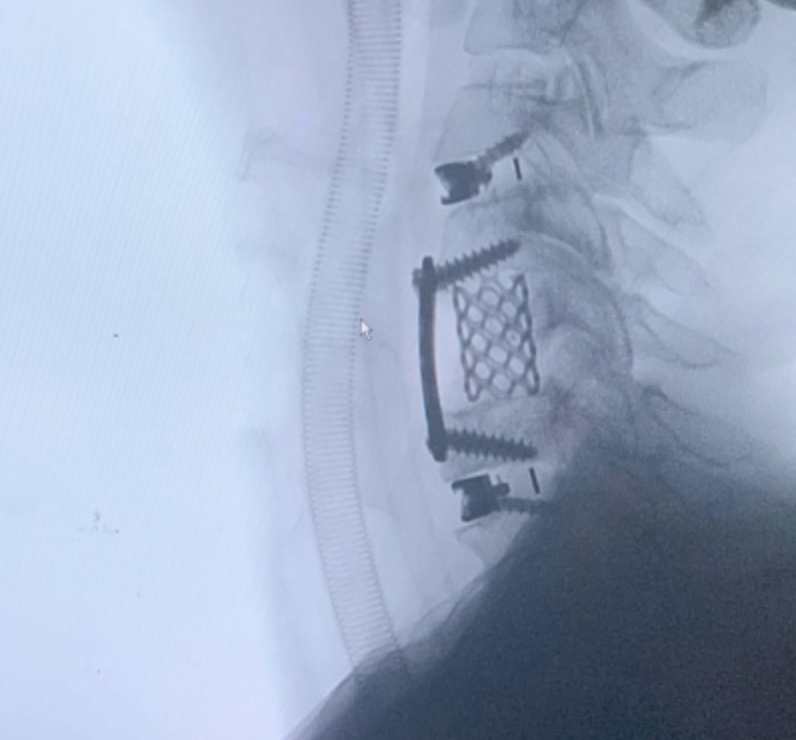

Cada procedimiento requiere una planificación detallada, basada en estudios de imagen y evaluación clínica, con el objetivo de lograr una descompresión adecuada de estructuras nerviosas y restaurar la estabilidad vertebral.

Se emplean técnicas quirúrgicas modernas, incluyendo abordajes mínimamente invasivos cuando son viables, lo que permite una recuperación más rápida y menor impacto en el paciente.